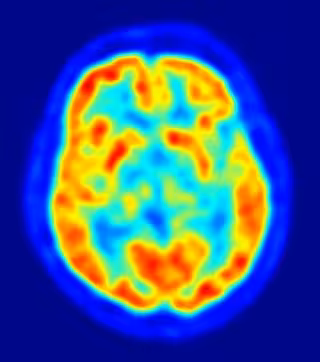

El Centro Superior de Investigaciones Científicas (CSIC) ha descubierto un gen, llamado Robo1, que consigue controlar el crecimiento de los axones, que son los que favorecen la aparición de enfermedades como la epilepsia y la esquizofrenia.

Y es que, los axones son las prolongaciones de las neuronas especializadas en conducir el impulso nervioso desde el cuerpo celular hacia otra célula. No obstante, para que la transmisión de los impulsos nerviosos que llevan a cabo las neuronas sea efectiva, estas deben estar correctamente conectadas a las regiones del cerebro susceptibles de recibir sus mensajes.

En concreto, el procedimiento se produce cuando los axones se acercan a la corteza cerebral, donde las células enviarán sus señales, y el gen Robot1, impulsado por una alteración de estas mismas señales eléctricas, consigue aumentar su expresión y ralentizar el crecimiento del axón.

Gracias a esta proyección axonal, las neuronas son capaces de transmitir la información visual, somatosensorial y auditiva que recibe el tálamo hacia las regiones concretas de la corteza cerebral dedicadas a procesar cada tipo de estímulo.